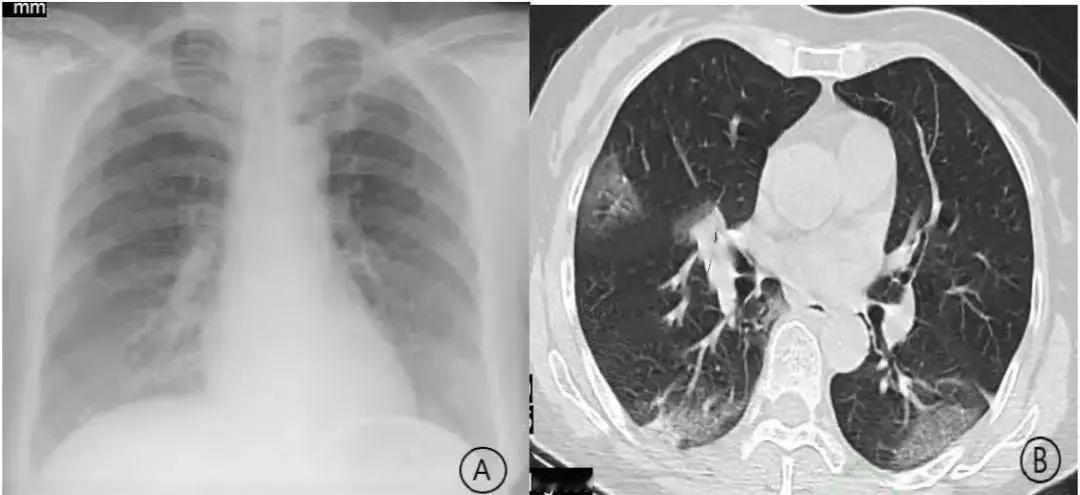

近日,河南4岁女童朵朵突发甲流合并细菌感染,24小时内病情急转直下,出现“白肺”并住进监护室。经紧急ECMO救治后转危为安。专家提醒,儿童免疫系统脆弱,甲流易继发细菌感染,出现持续高热、呼吸急促等症状需立即就医。预防甲流